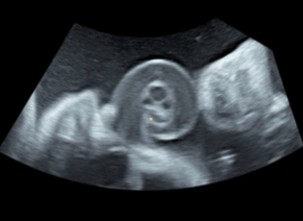

Paciente de 28 años en la que, durante el ultrasonido realizado por medicina materno-fetal a las 33,1 semanas de gestación, se encontró un patrón de imagen en trébol en el área libre del cordón umbilical (Figura 1).

La primera descripción por ecografía de un nudo verdadero de cordón umbilical fue reportada por Collins en 1991, como una imagen con patrón en hoja de trébol 2. Cuatro años más tarde, en un estudio retrospectivo, se sugiere que este o un patrón multicolor inusual pueden ser sospechosos, pero inespecíficos para el diagnóstico de un nudo verdadero de cordón 3.